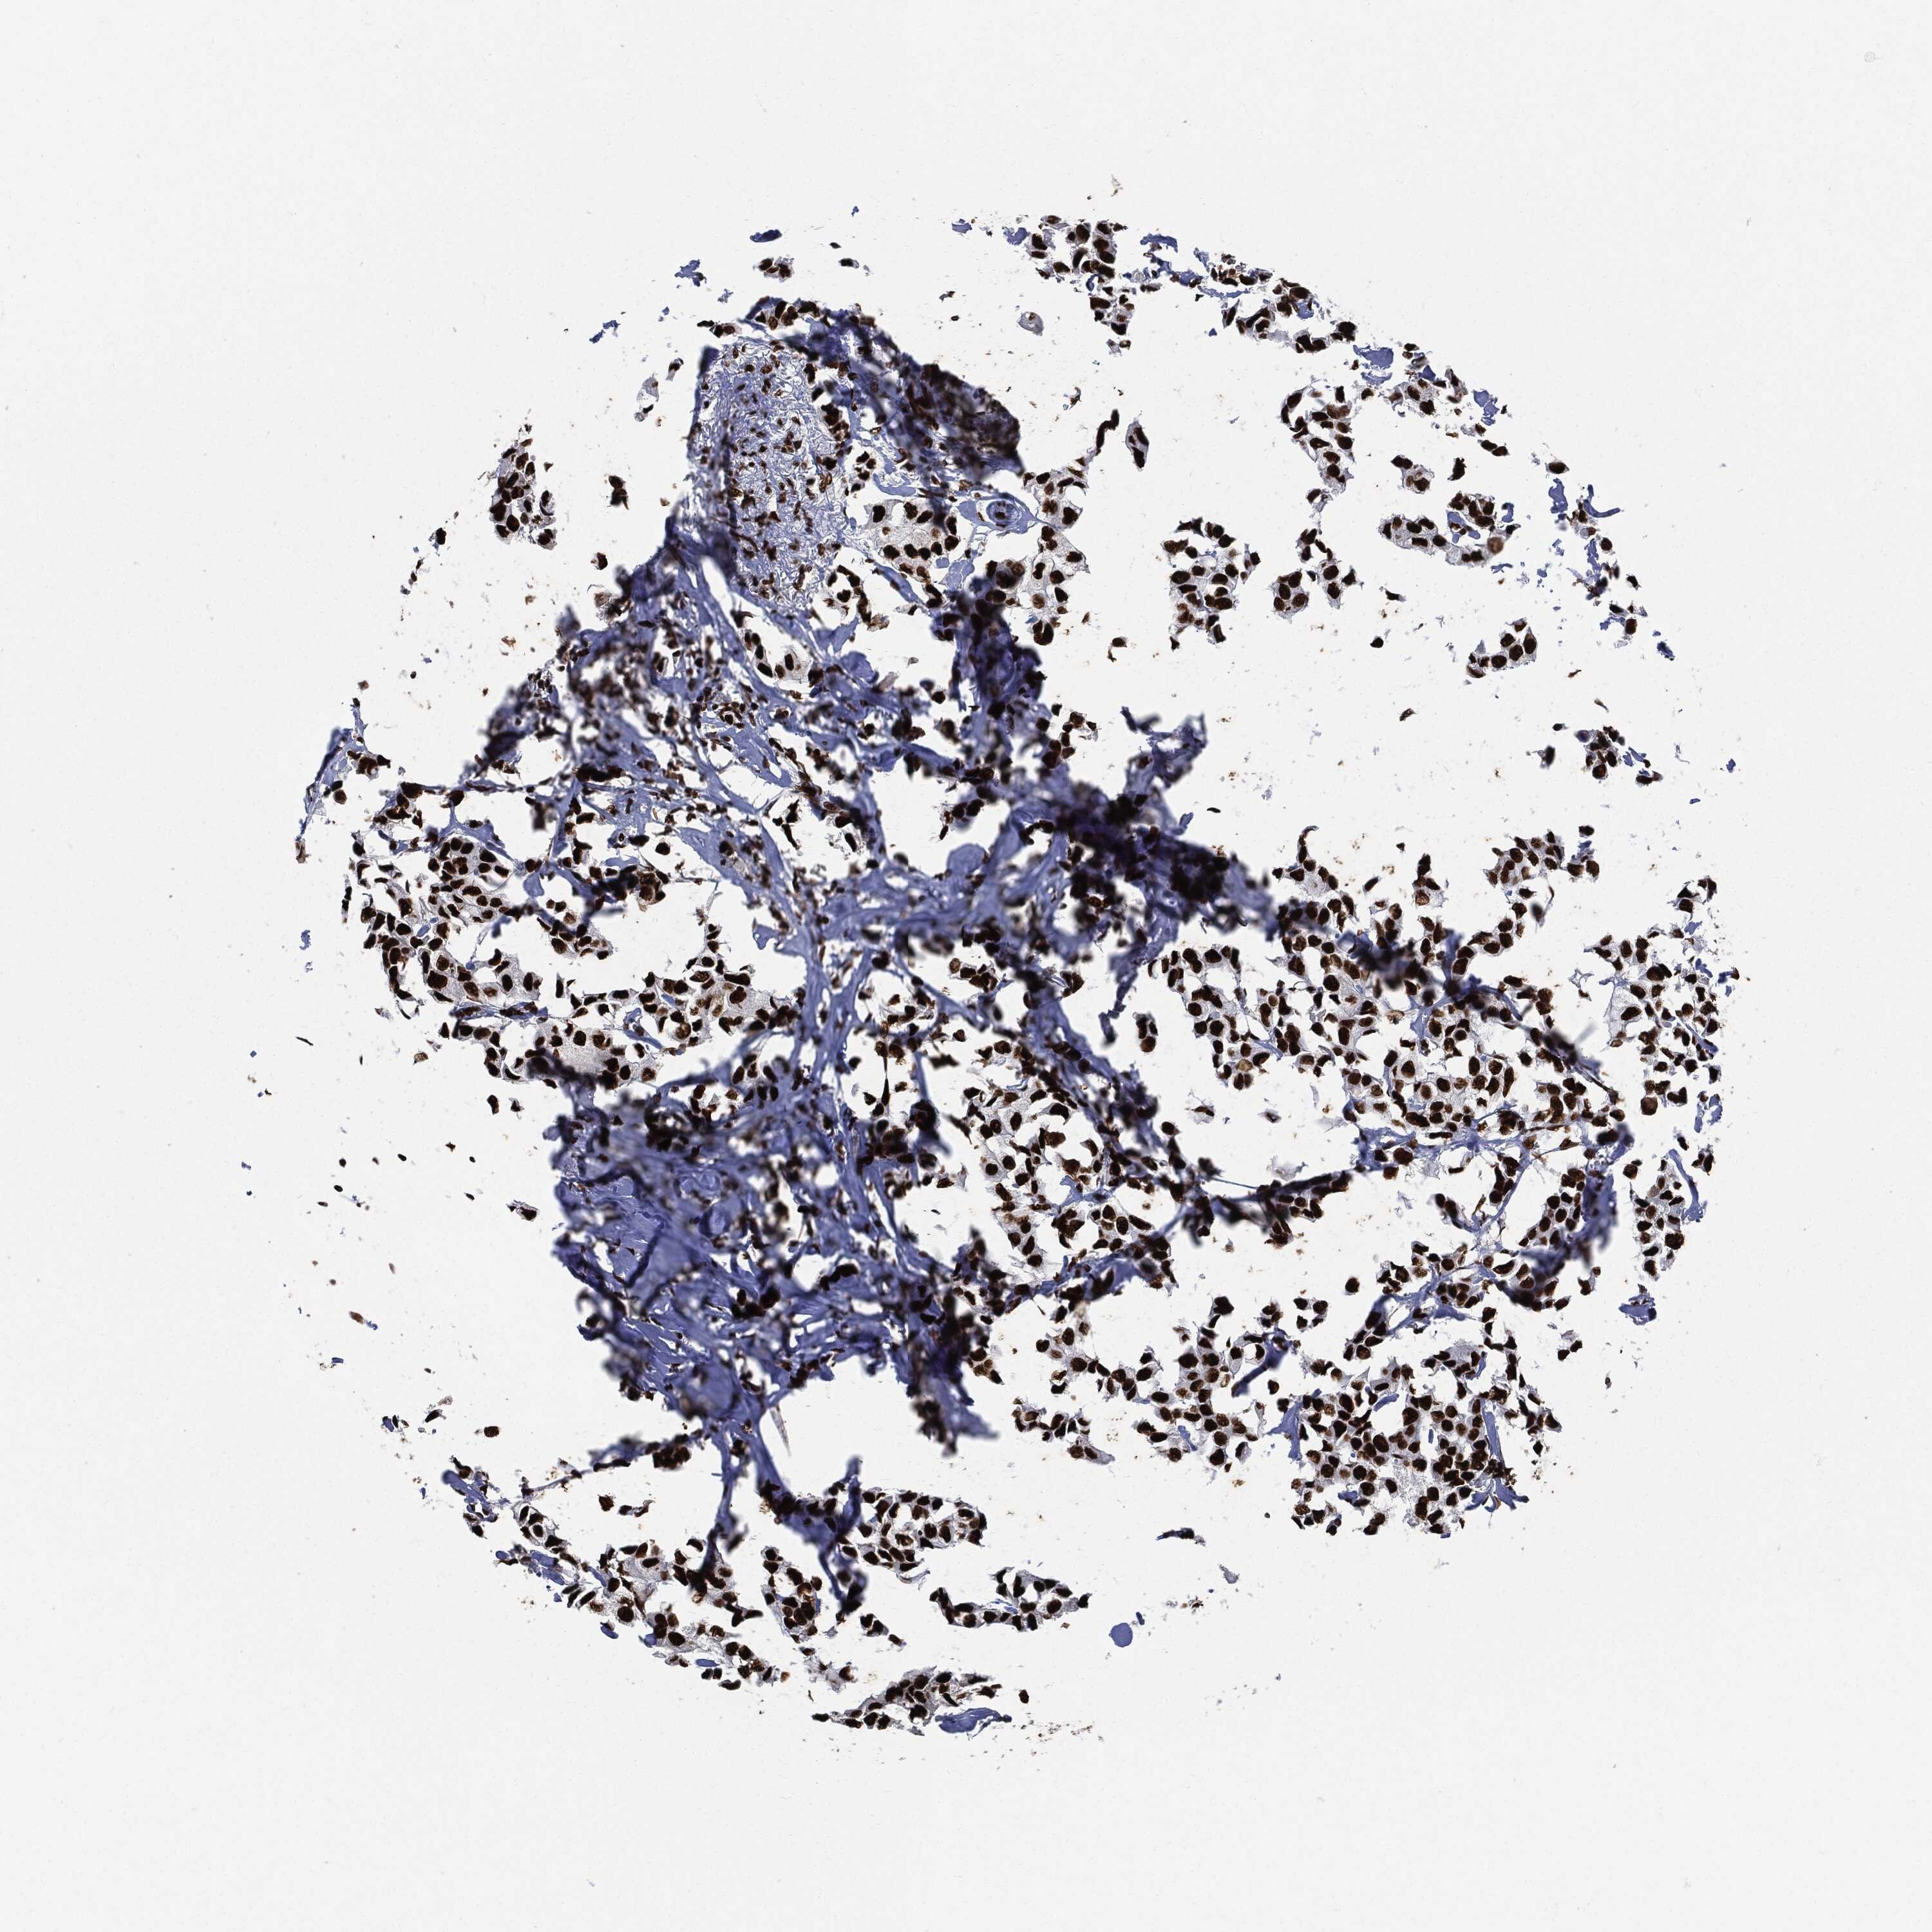

BRCA TCGA BRCA VALIDATION PROTEIN EXPRESSION